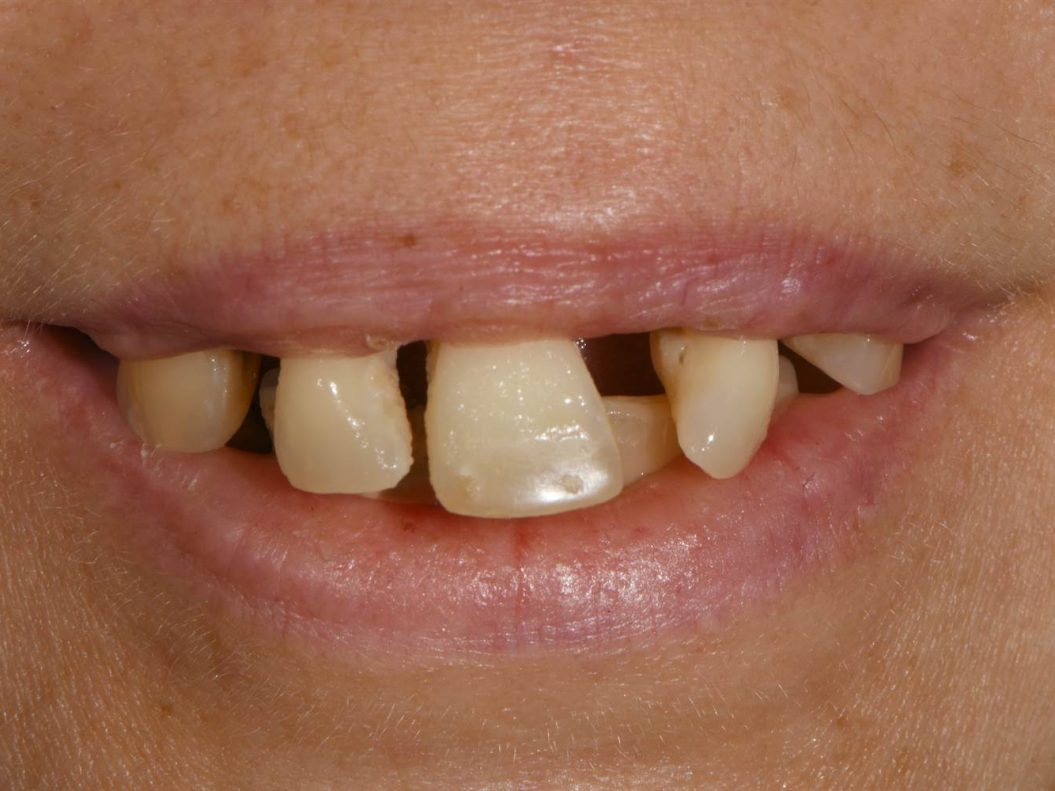

- Fotografia dello stato iniziale